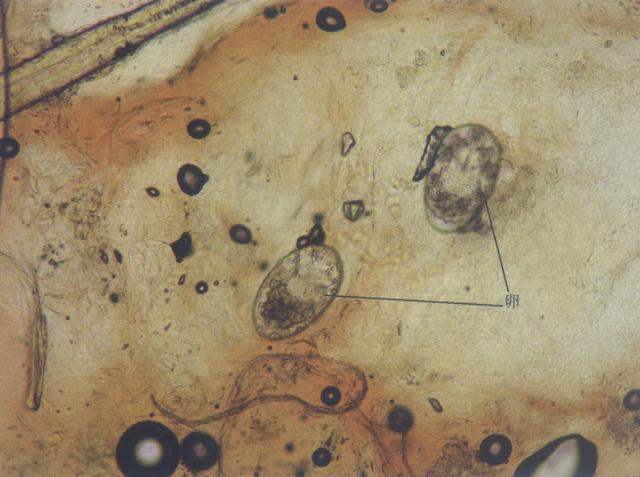

icon疥螨的卵(犬,油法透明化,400×)

疥螨的卵(犬,油法透明化,400×)

资源描述:2个疥螨的卵(犬,油法透明化)(400×)